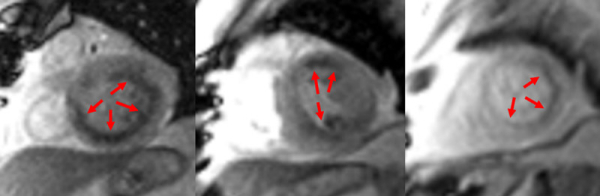

Figure 6 : Séquence de perfusion premier-passage au stress

Coupes petit-axe basal (A), médian (B) et apical (C)

On peut noter deux types d’hypoperfusion distinctes (flèches rouges) :

- une hypoperfusion sous-endocardique inféro-latérale correspondante à la séquelle d’IDM inféro-latéral déjà connue en 2011

- une hypoperfusion sous-endocardique de 2-3 segments sur 17 en antéro-basal et antérolatéral correpondant à une ichémie inductible.

Pour rappel : la définition d’une ischémie myocardique inductible est la présence d’une hypoperfusion sous-endocardique au stress SANS présence d’un rehaussement tardif dans la même zone.